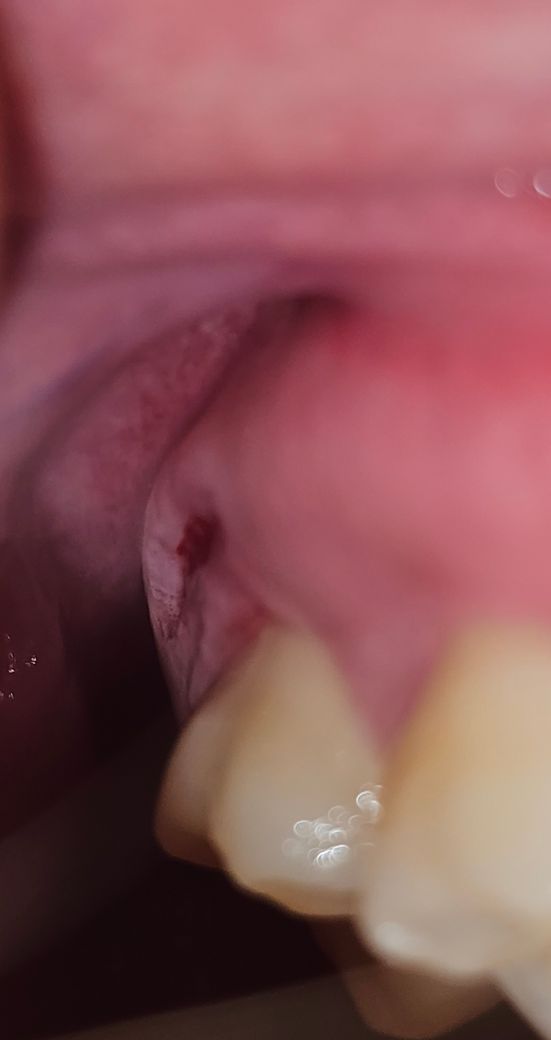

잇몸이 파여있음과동시에 통증이 옵니다

며칠전부터 위에 바깥쪽 뒤에있는 잇몸쪽이 점점 움푹 들어가서 손으로 좀 건드렸더니 피도납니다. 파인부분에 뼈같은 딱딱한 것도 느껴지는데 사랑니가 나오는중인건가요? 근데 이 위치에 나오는게 맞는지 싶고.. 밑에는 통증부위 사진입니다

• 1번 째 사진

잇몸이 안으로 푹 들어간 이유를 찾아야 될 것으로 생각됩니다. 사랑니가 나올 부위는 아닌 것으로 보이며 음식을 먹다가 해당 부위에 자극이 되었거나 손상을 받았을 가능성이 높습니다.

파인 부위에서 딱딱한 느낌이 나는 경우 사랑니가 나오고 있는 것일 가능성이 높으며, 사랑니가 나오는 과정에서 잇몸에 압력이 가해져 잇몸이 파이거나 붓는 경우가 종종 있습니다.

농양이 잡혀 피고름이 나오고 있는 것이 아닐까 의심되며 치과에 가서 검사를 통해 원인 치아나 잇몸을 찾아봐야 합니다